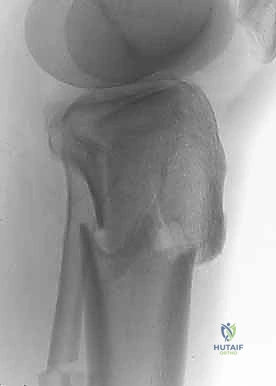

2. التصوير الإشعاعي (X-rays)

الخطوة الأولى هي التقاط صور أشعة سينية من عدة زوايا (أمامية خلفية، وجانبية). تعطي الأشعة السينية فكرة عامة عن وجود الكسر وموقعه، لكنها غير كافية لتقييم الكسور ثنائية اللقمة المعقدة.

3. الأشعة المقطعية المحوسبة (CT Scan) - المعيار الذهبي

لا يمكن إجراء جراحة لكسر ثنائي اللقمة دون إجراء أشعة مقطعية (يفضل مع إعادة بناء ثلاثية الأبعاد 3D).

* توفر الأشعة المقطعية خريطة دقيقة لكل شظية عظمية.

* تحدد مقدار الانخساف في السطح المفصلي بالمليمتر.

* تكشف الشظايا المخفية، خاصة في الجزء الخلفي من الركبة (Posterior Coronally oriented fragments) والتي تتطلب خطة جراحية خاصة لتثبيتها.